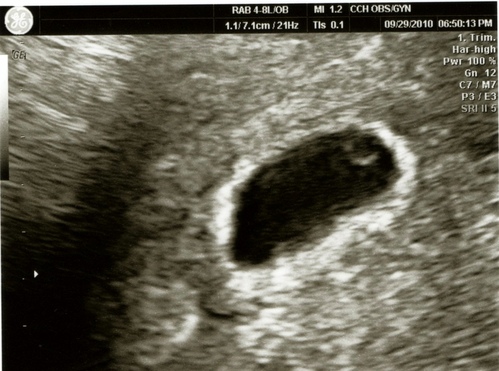

99年9月29日 Wed. 去醫院確認懷孕

星期三承芳去產檢,我就跟著去讓醫生確定是否懷孕。

大醫院的熱門醫生總是要等好久,終於輪到我照超音波,醫生沒有兩秒就說我是懷孕了。

大約才五週,還沒有心跳,只確定了是子宮內懷孕。

預約下一週再去看有沒有心跳。

於是我又提心吊膽了一個禮拜,很怕是葡萄胎之類的。